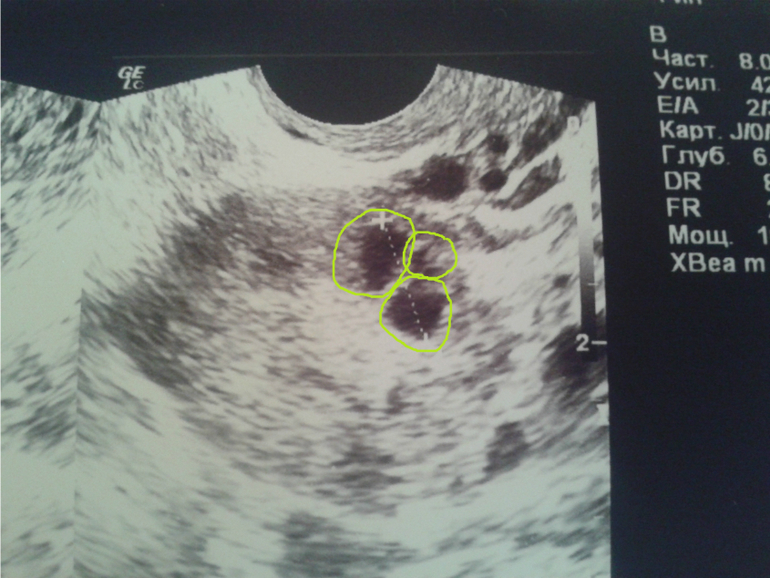

внутри какие то перегородки появились, да не одна, а две, т.е. он как бы состоит из 3-х фолликулов, габаритный размер 11,6мм, эндик 10,5мм

ну то что он пытался лопнуть я поняла

может он только что лопнул и поэтому такой корявый?